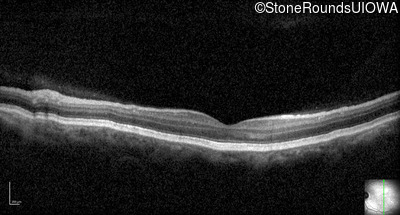

Optical Coherence Tomography - Left - 20/200

Exemplar / OCT Stack

OCT Stack